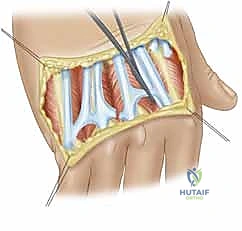

- التهاب الغشاء الزليلي (Synovitis): يبدأ المرض بالتهاب الغشاء الزليلي، وهو الغشاء الرقيق الذي يبطن المفصل ويفرز السائل الزليلي للتشحيم. في مريض الروماتويد، يتكاثر هذا الغشاء بشكل مرضي ويصبح سميكاً جداً.

- تكوين السبلة (Pannus Formation): يتحول الغشاء الزليلي الملتهب إلى نسيج عدواني يُعرف باسم "السبلة" (Pannus). هذا النسيج يفرز إنزيمات مدمرة (مثل الميتالوبروتياز) تأكل الغضروف المفصلي الناعم وتسبب تآكلات (Erosions) في العظام تحت الغضروف.

- تمدد المحفظة والأربطة (Capsular Distension): التورم المستمر وتراكم السوائل والسبلة داخل المفصل يؤدي إلى تمدد وضعف المحفظة المفصلية والأربطة الجانبية، مما يفقد المفصل استقراره الثابت.